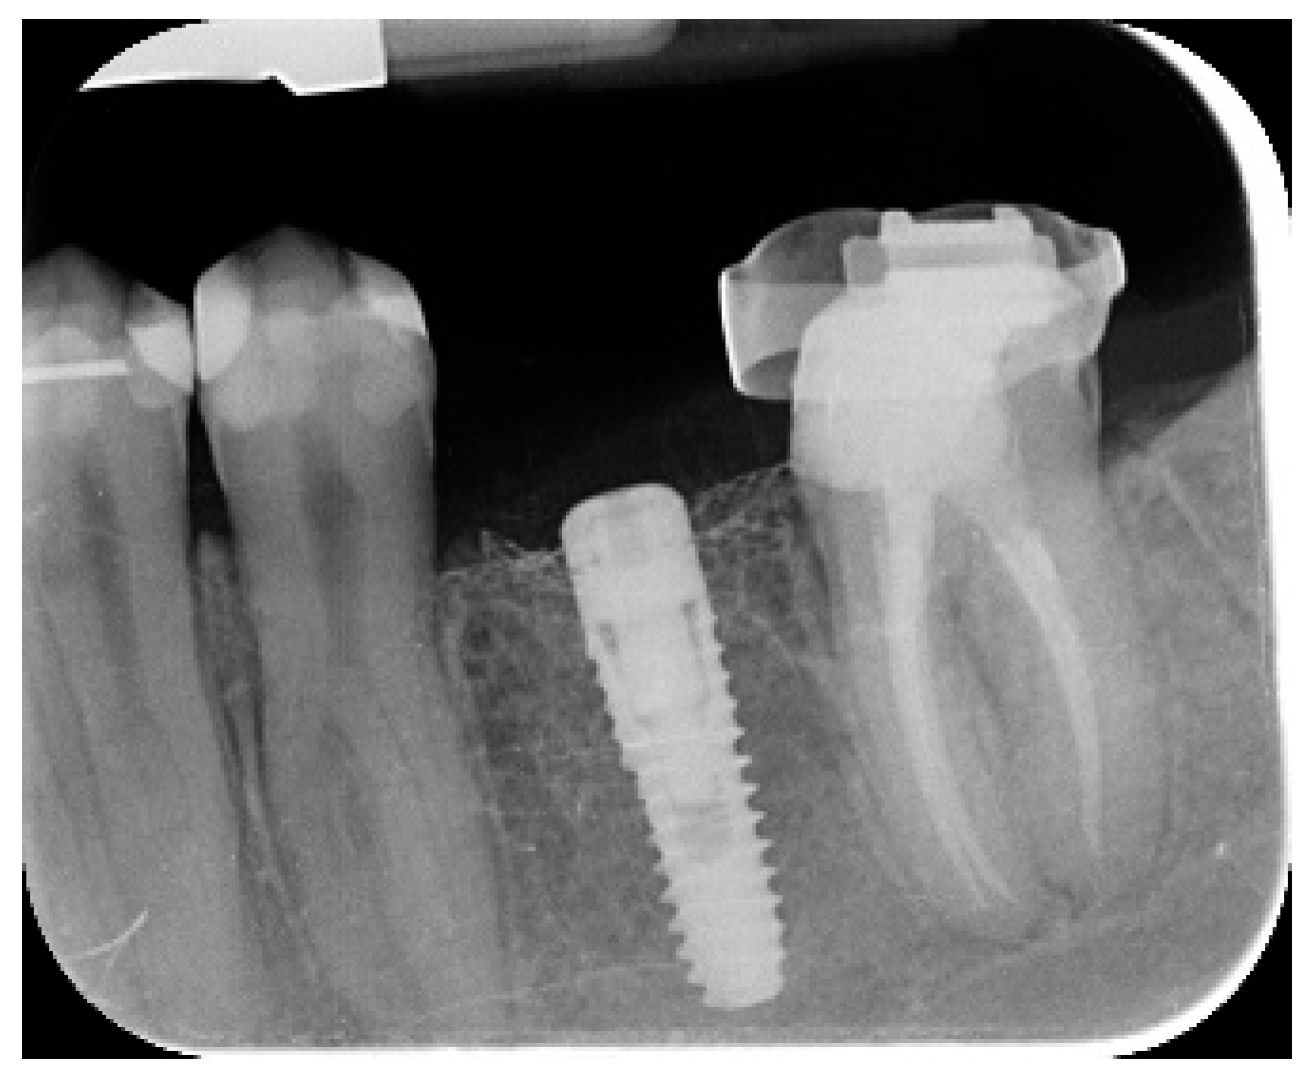

- Marginal bone level changes were assessed by digital periapical radiographs (Digora Optime; Soredex, Tuusula, Finland) using the parallel technique and commercially available film holders. Three time points were evaluated, at implant placement (baseline), immediately after the insertion of the restoration, and one year after loading. The averaged mesial and distal distances from the most coronal margin of the implant and the first bone-to-implant contact was measured to the nearest 0.01 mm and taken as the marginal bone level. The difference in levels between time points was taken as marginal bone loss (MBL).

| Mean marginal bone loss (mm) | 0.13 ± 0.09 (95% CI 0.08–0.19) | 0.28 ± 0.33 (95% CI 0.07–0.50) |